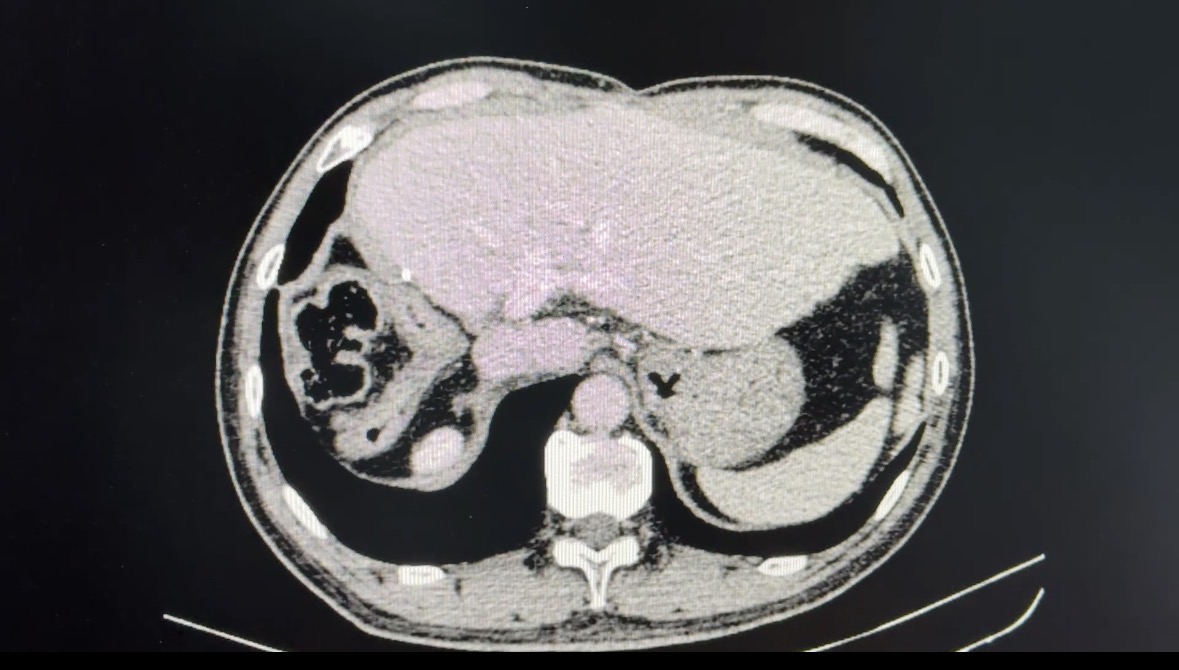

Hình ảnh phim chụp cắt lớp vi tính u lớn gan phải kèm huyết khối tĩnh mạch cửa lan vào thân chung và tĩnh mạch cửa trái của người bệnh N.T.Đ